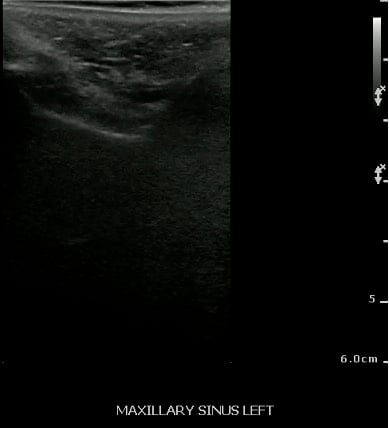

- Normal Maxillary Sinus:

- The normally air-filled maxillary sinus prevents the transmission of ultrasound beams (Air reflects most of the signal, thus preventing visualization of deep structures).

- The anterior maxillary sinus wall produces a bright echo in the near field, with reverberation artifact posteriorly (producing a snowstorm appearance), and preventing visualization of the posterior wall.

- Figure 27 and 28. Normal maxillary sinus